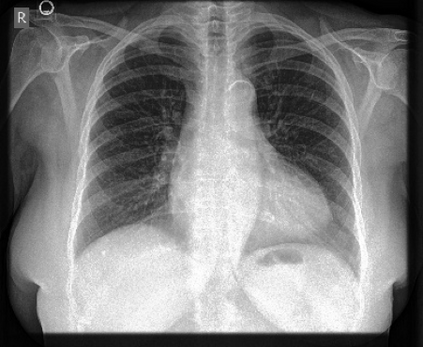

The availability of large public datasets and the increased amount of computing power have shifted the interest of the medical community to high-performance algorithms. However, little attention is paid to the quality of the data and their annotations. High performance on benchmark datasets may be reported without considering possible shortcuts or artifacts in the data, besides, models are not tested on subpopulation groups. With this work, we aim to raise awareness about shortcuts problems. We validate previous findings, and present a case study on chest X-rays using two publicly available datasets. We share annotations for a subset of pneumothorax images with drains. We conclude with general recommendations for medical image classification.